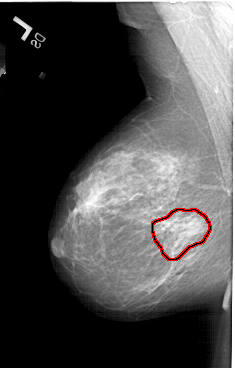

A_1217_1.LEFT_CC

FILE: A_1217_1.LEFT_CC.OVERLAY

TOTAL_ABNORMALITIES 1

ABNORMALITY 1

LESION_TYPE MASS SHAPE ARCHITECTURAL_DISTORTION MARGINS SPICULATED

ASSESSMENT 4

SUBTLETY 2

PATHOLOGY MALIGNANT

TOTAL_OUTLINES 1

BOUNDARY